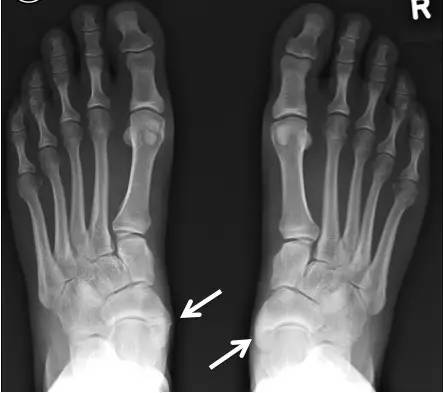

副舟骨和扁平足之间有很大关系。

一方面,改变胫骨后肌的发力方式,使前足内收足弓降低。另一方面,当足内翻时会撞击内踝,为缓解疼痛患者会采取足外翻的姿势,进一步引起足弓降低。

儿童如果存在平足,在骨化时副舟骨会向下向内侧移位。